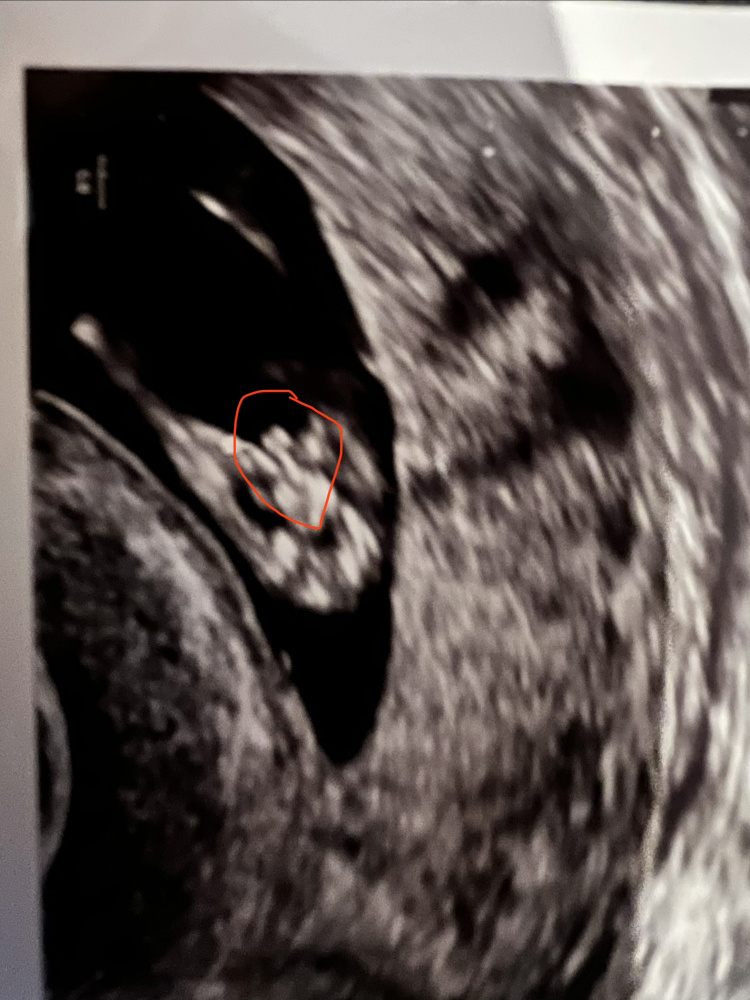

Mein Frauenarzt hat mir in 11+4 SSW ein Jungenouting gegeben. Allerdings sagte er, er sieht was zwischen den Beinen und ist gespannt ob er recht hat…

Aber so früh sehen sich Jungs und Mädchen doch sehr ähnlich oder?

Oder meint ihr man sieht da auch die hoden? 🙊

Ich Heft euch mal das Bild ran…